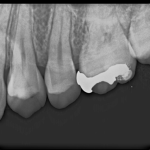

口腔内写真と歯科用レントゲン

口腔内所見では少し歯が黒いのかな?また、レントゲンでもはっきりとは映ってはいないが、診査診断を行うことで早期の治療を話をした。